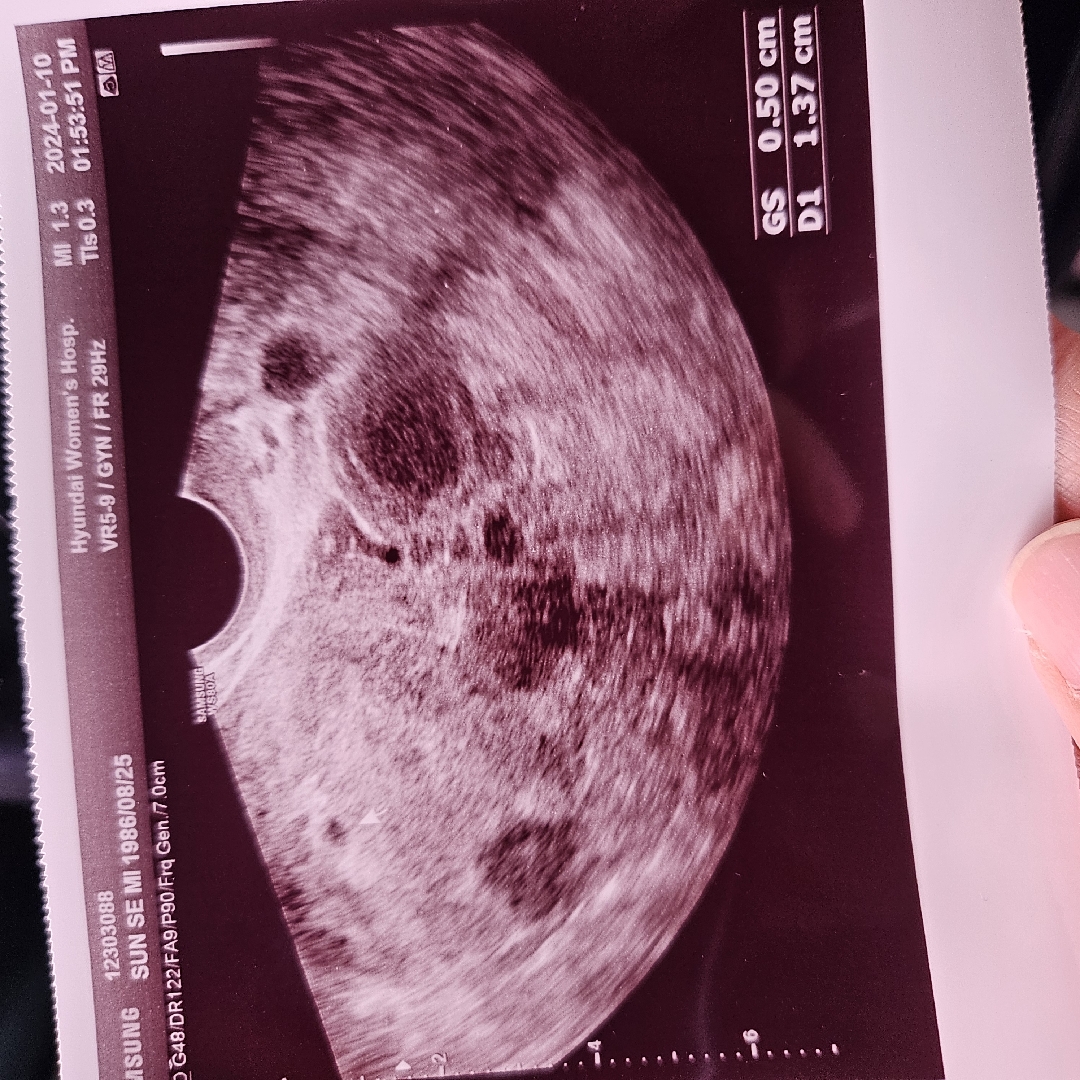

작년5월에 임신했는데 고사난자로 이별하고 9월엔 화유 ㅠ 맘편히 갖자 생각했는데 새해부터 찾아왔어요~~ 12월1일 막생이고 워치6로 체온재면서 예상베란일에 숙제했는데 1월1일 생리예정일엔 2줄 안나오더라구요 생리지연됐나 생각했는데 기다려도 소식이 없어서 어제 얼리패스터 해보니 2줄... 오늘 아침에도 2줄.... 의사쌤이 5주는 맞는데 2-3일전에만 와도 안보였다고 3주전에 관계로 생긴거라는데 18일, 22일 관계해서 12월 22일에 생겼나 싶어요 화유도 경험해봐서 넘 긴장되요 2주동안 잘 지내고 있어야되는데 임신/출산 진료비 지급신청서도 주셔서 몸관리 잘해서 잘 낳아야지 생각하는데 작년에 2번이나 실패해서 너무 겁나요